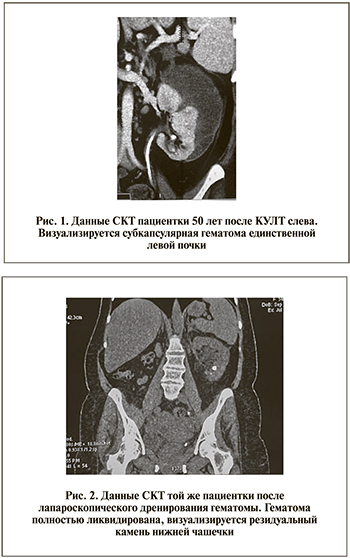

П а ц и е н т к а 50 лет госпитализирована в клинику урологии в экстренном порядке с диагнозом: почечная колика слева и постренальная анурия. В анамнезе нефрэктомия справа в связи с терминальным гидронефрозом на фоне обтурирующего камня мочеточника. Слева ей дважды выполнена перкутанная нефролитотрипсия по поводу коралловидного нефролитиаза, последняя из которых была 8 мес. назад. После данной операции в нижней передней чашечке оставался резидуальный камень диаметром 10 мм. При обследовании в анализах крови обращали внимание анемия (гемоглобин 90 г/л), повышение уровня креатинина до 250 мкмоль/л и мочевины до 15 ммоль/л. На томограмме видно, что камень из нижней чашки мигрировал в верхнюю треть мочеточника. Была проведена уретероскопия ригидным уретероскопом с лазерной литотрипсией камня и установлен стент 6 Шр. На 2-е сутки появились боли в области левой почки, температура тела повысилась до 38,5°С. При УЗИ и по данным СКТ выявлена гематома левой почки больших размеров (рис. 1).

В настоящее время ее общее состояние стабильное (креатинин крови – 106 мкмоль/л, гемоглобин – 136 г/л). При контрольной СКТ размеры левой почки нормальные, паренхима ее сохранена, резидуальный камень в нижней чашечке, гематомы нет (рис. 2).